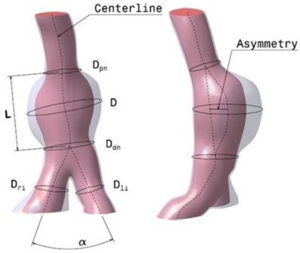

The primary goal of this further work was to motivate a new phenomenological approach for identifying regions of possible formation of Intra Luminal Thrombus (ILT) on an intact but susceptible endothelium within AAAs. Following the idea of paper 2, CFD Modelling of Abdominal Aortic Aneurysm on Hemodynamic Loads using a Realistic Geometry with CT, thirteen new patients with infrarenal aneurysms from Clinical Hospital of Valladolid (Spain) have been studied. The patients chosen for this study were selected during the first stages of the AAA's development. All the patients who participated in this trial analysis volunteered and provide written consent to be part of the study. This study was reviewed and approved by the Ethics Committee of the Clinical Hospital of Valladolid (Spain). To characterize the AAA shape and size, the main geometrical AAA parameters were determined using the lumen center line [66][26] of the segmented images. Twelve indices were defined and computed for the thirteen AAA patient-specific models. Figure 13 shows the seven geometrical parameters defined (AAA morphometry).

Another four geometrical indices[15] were defined: (saccular index) assesses the length of the AAA region, this region will be affected by the formation and further development of the ILT, (deformation rate) characterizes the deformation of the aorta, relation between D and D, (tortuosity index) is the ratio of the length of the curve to the distance between the proximal and distal neck and (symmetry index) is the result of the non-symmetry expansion of the aneurysm sac. Next table 1 shows the parameters for the 13 new cases analyzed.